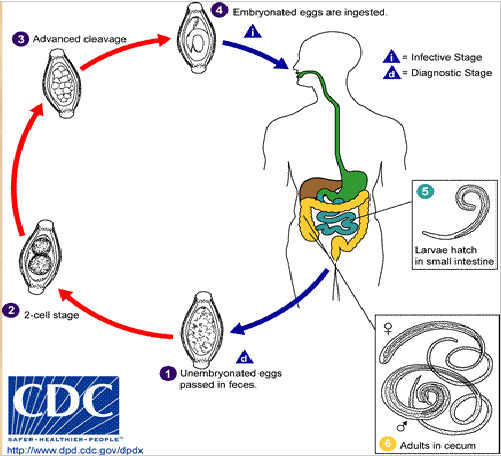

life cycle of trichuris trichiura

unembryonated eggs passed in feces

goes through 2 cell stages & eventually advanced cleavage

ingestion of embryonated eggs by definitive host

larvae hatch in small intestine

adults live in cecum of intestine

trichuris trichiura eggs

54 x 22 um

Distinct barrel shape

Refractile, convex, hyaline polar plugs at both ends

Unembryonated internal mass

answer the following about t trichiura:

What form is shed/acquired from the human?

If, an egg, is it embryonated or not?

If it is a larvae, what kind of larvae?

What hatches from the egg?

unembryonated egg shed from human

goes through two-cell stage and hatches into larvae AFTER human has ingested the embryonated eggs

answer the following about t trichiura:

intermediate host? reservoir host?

What is the infective stage that gets back into the human?

How does the infective stage get back into the human?

General info about what happens once it gets back into the human.

Where do adults live?

no intermediate host; reservoir: humans/primates

infective stage: embryonated egg

humans ingest embryonated egg from contaminated food/water

larvae hatch in small intestine

adults live in the cecum